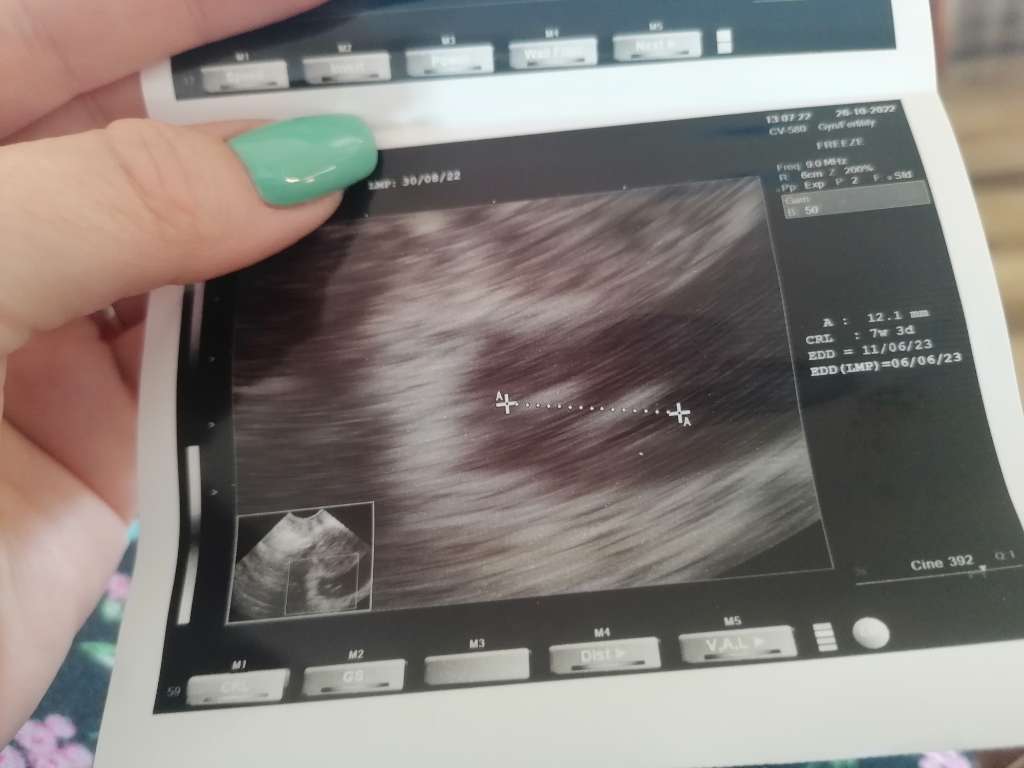

Nie wiedziałam czy pisać, czy nie pisać, ale jednak... Miałam wizytę na 12. I sama nie wiem co myśleć, ale staram się myśleć pozytywnie, bo każdy każe mi tak myśleć i się niczym nie przejmować :) Ale przejdę do meritum... Na usg wyszło, że jest już zarodek, ma 12 mm, a co do serduszka... Lekarz widział serduszko, ale tak jakby słabo, mówił, że może się gdzieś chowa, że może jeszcze za wcześnie i następną wizytę wyznaczył na 9 listopada. Słuchajcie zastanawiałam się nad tym, bo wedle OM wychodzi, że mam 8+1, ale chyba 2 tygodnie się odejmuje, więc 6+1, ale ja też mam bardzo długie i nieregularne cykle od 32 do 38 dnia, a owulacje miałam też w 19 dniu, więc może to tak naprawdę dopiero 5+6? Lekarz mówił, że mam się nie martwić, przyjść za 2 tygodnie i będzie już wszystko widać. Chodzę na nfz, ale nie wiem czy iść prywatnie, bo bardzo lubię tego lekarza, jest dobry, pytałam go nawet o te usg, że podobno przysługują tylko 3 na nfz, a on powiedział do mnie: to co mówią to jedno, ale dobry lekarz zrobi tyle ile potrzeba, zrobię Ci tyle usg i tyle badań, byś czuła się bezpiecznie i by wszystko było dobrze z ciąża. Powiedzcie co o tym wszystkim myślicie, a ja załączam zdjęcie USG.